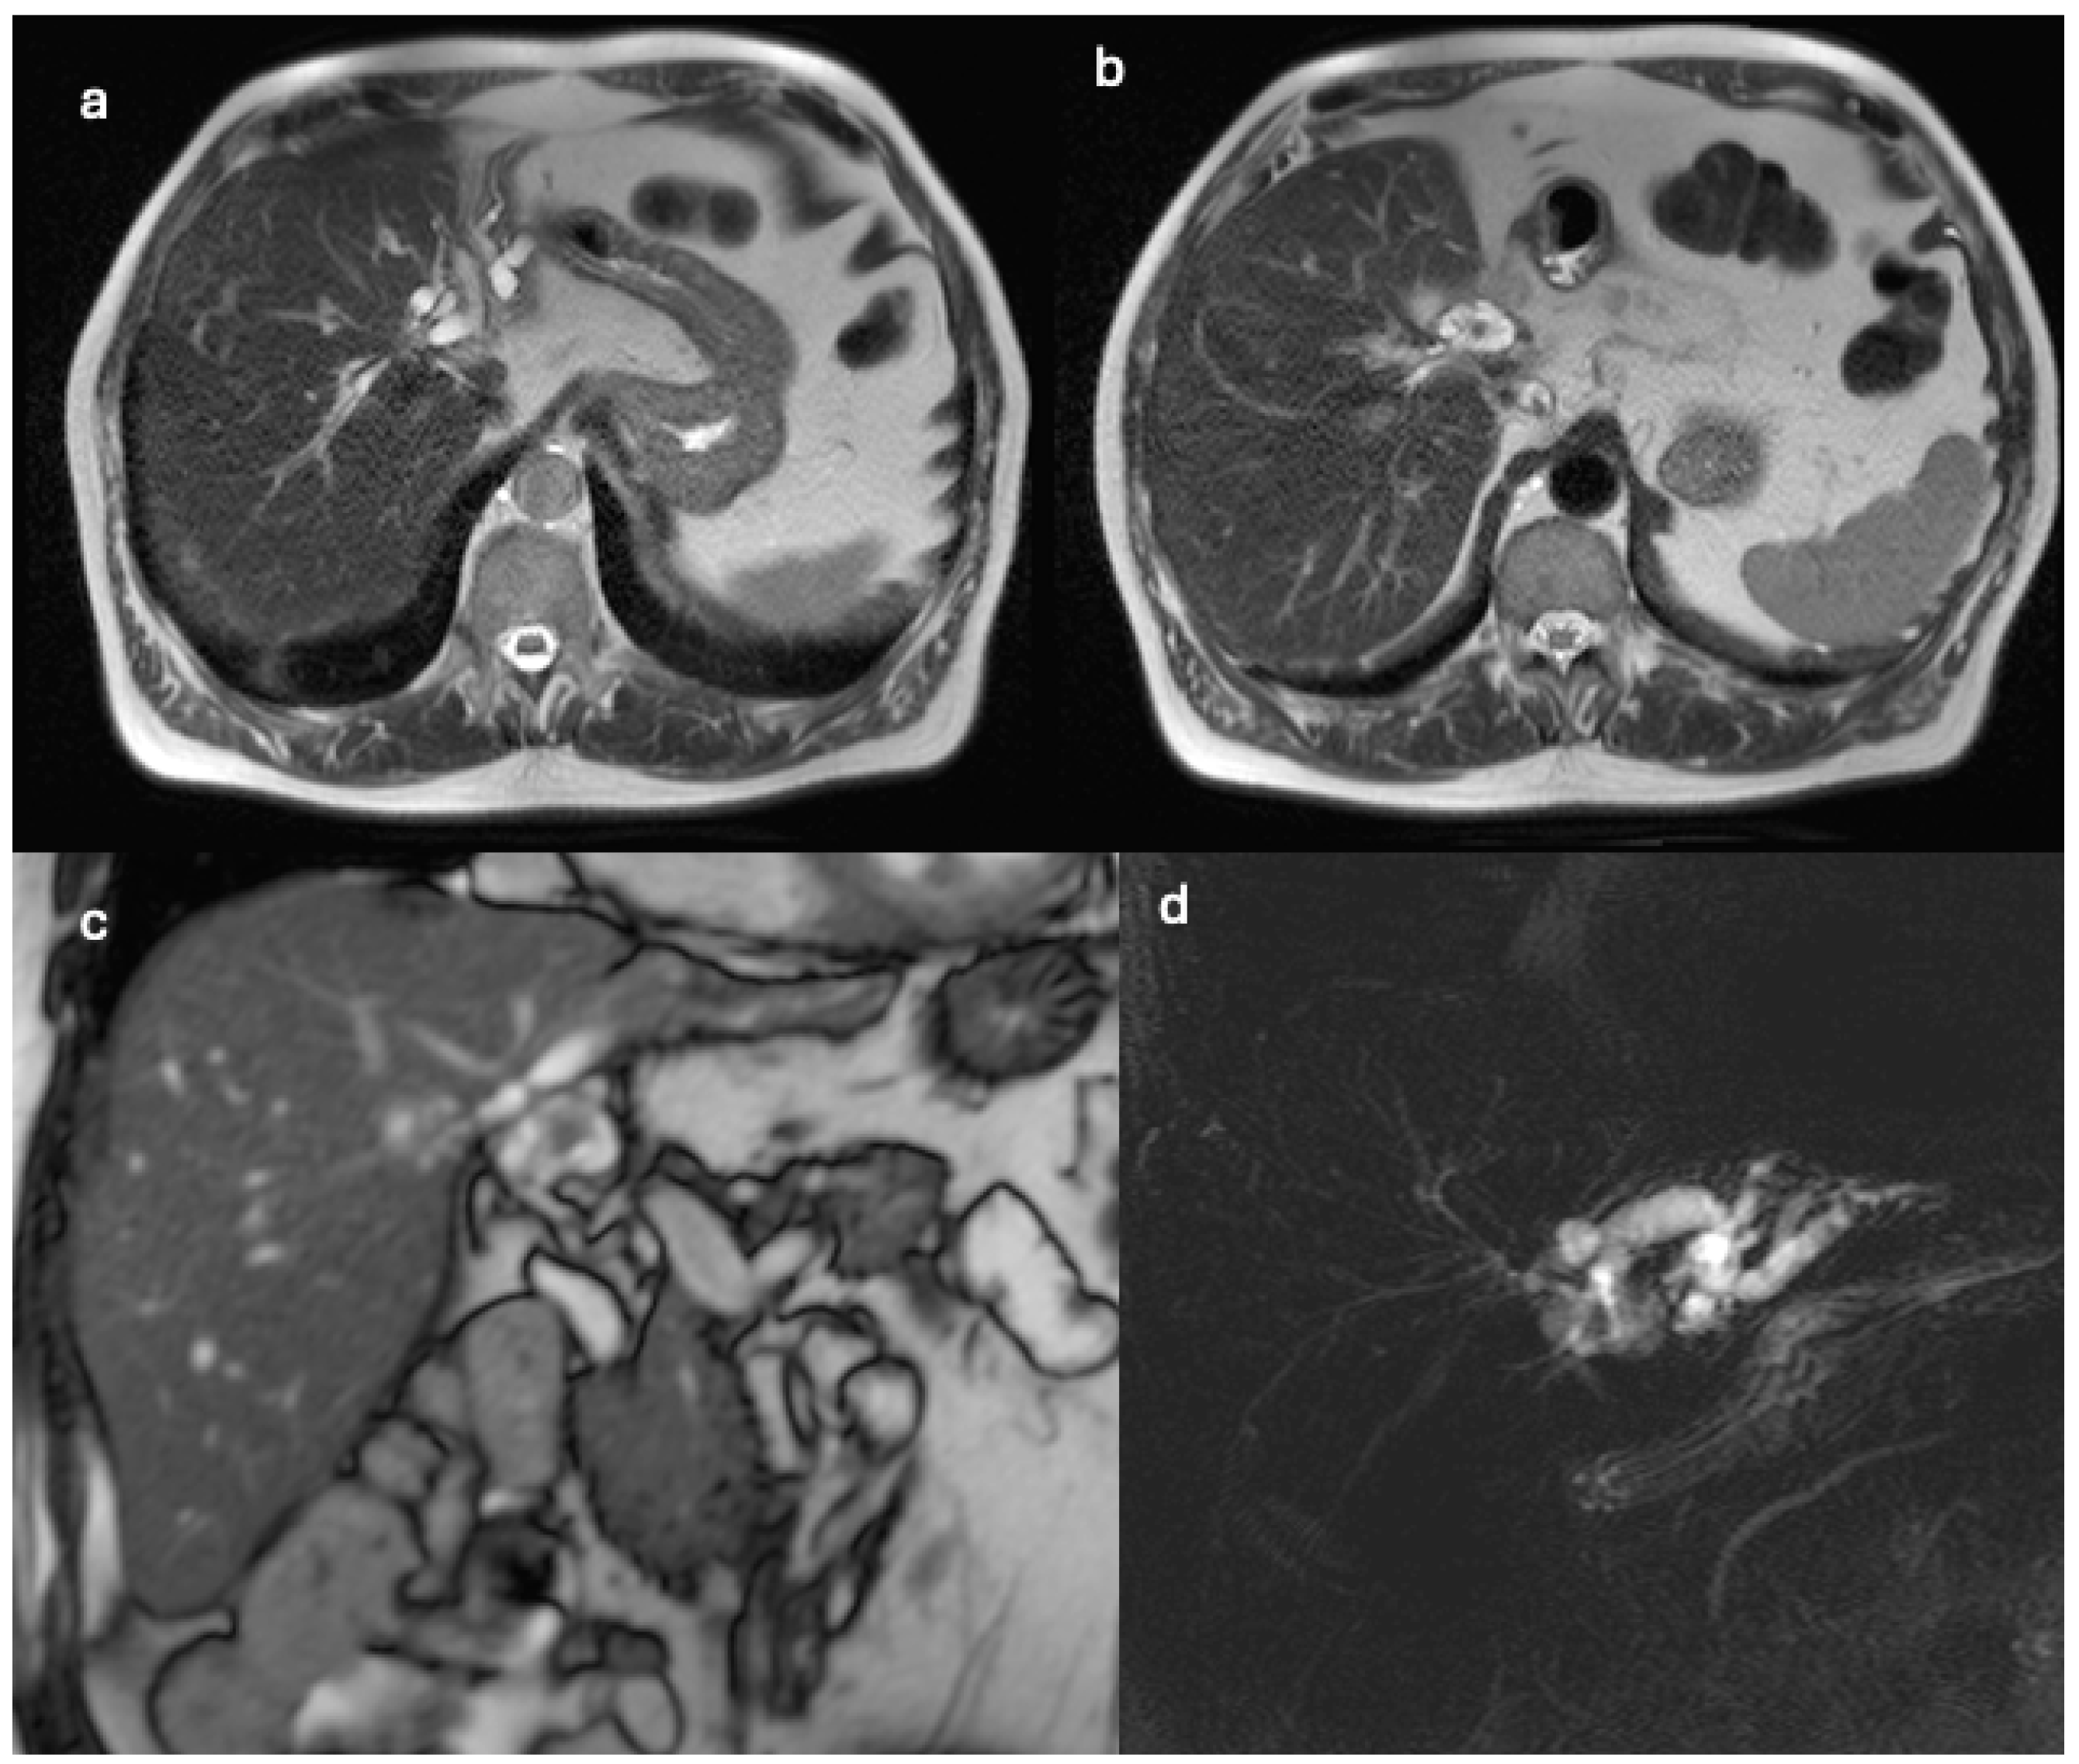

| Diagnostic Methods | MRI, MRCP, ERCP, histopathological examination | CT, MRI, laparoscopic liver biopsy, histopathological examination |

| Tumor Characteristics | Large cystic mass, thin walls, internal septa, papillary projections, enhancing solid components | Large lesion in left hepatic lobe, hyperintensity in T2-weighted images, restricted diffusion, contrast enhancement |